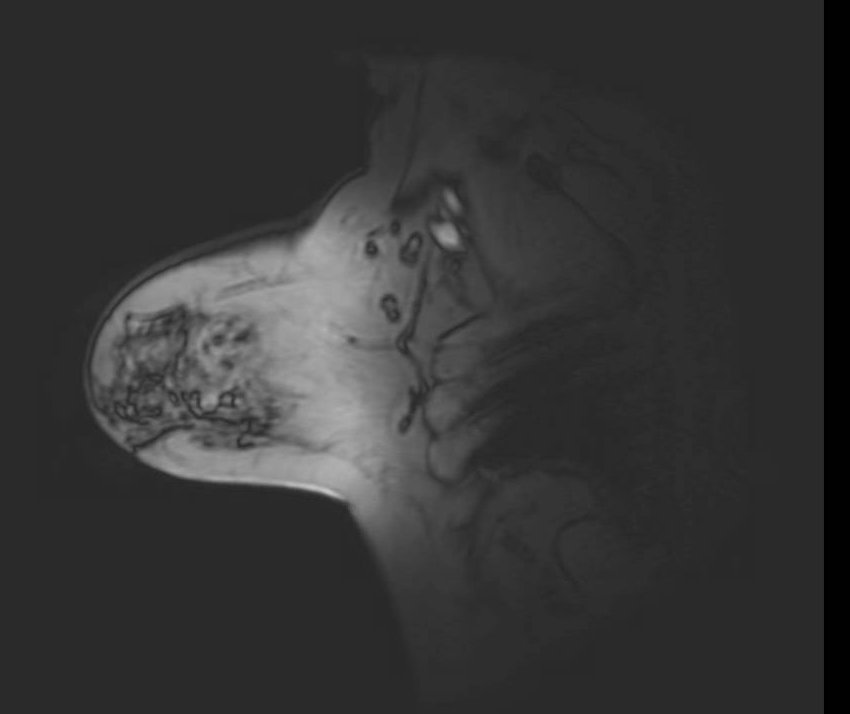

Fat Sat / B0 - Port

Unilateral fat suppression failure secondary to port-o-cath. Axial fat-saturated T1-weighted image demonstrates failure of fat suppression in the right breast with preserved suppression on the left. In addition to the focal signal dropout at the port site, the opposite side of the right breast demonstrates diffuse high signal intensity (bright fat), reflecting regional off-resonance that shifts fat signal outside the suppression bandwidth. This pattern indicates a broader ipsilateral B0 perturbation rather than an isolated focal device effect.